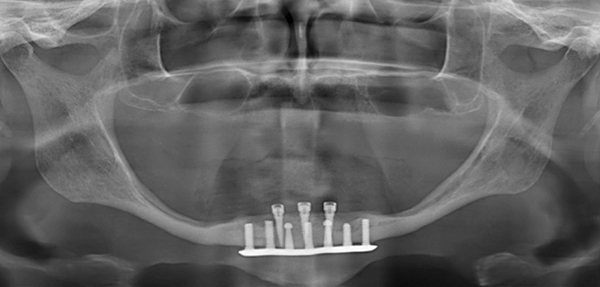

The rehabilitation of failing implant-supported overdentures often can become a complicated endeavor. The task of restoring a case in which the implant(s) is fractured or is old and has been discontinued with no replacement parts available frequently is quite problematic.

Anthony P. Prudenti, DDS, MS; et al